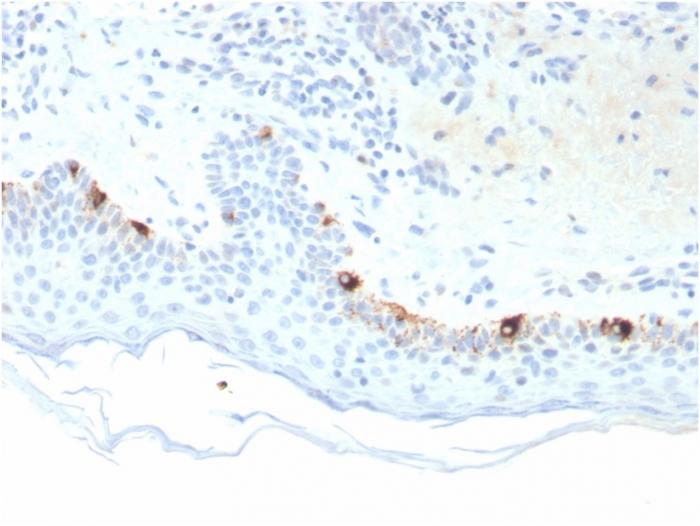

Positive Control

SK-MEL-23, SK-MEL-19, SK-MEL-30, SK-MEL-37 cells. Human Skin or Melanoma.

Reacts with a 75 kDa melanocyte-specific gene product, identified as Tyrosinase-related protein-1 (TRP-1). It is involved in melanin synthesis. TRP1 is present on the melanosomal membranes of melanoma, normal melanocytes and nevi. Recent evidence suggests that TRP-1 is involved in maintaining stability of tyrosinase protein and modulating its catalytic activity. TRP-1 is also involved in maintenance of melanosome ultrastructure and affects melanocyte proliferation and cell death. Primary antibodies are available purified, or with a selection of fluorescent CF® Dyes and other labels. CF® Dyes offer exceptional brightness and photostability. Note: Conjugates of blue fluorescent dyes like CF®405S and CF®405M are not recommended for detecting low abundance targets, because blue dyes have lower fluorescence and can give higher non-specific background than other dye colors.

IHC, FFPE (verified)

IHC (FFPE) (verified)